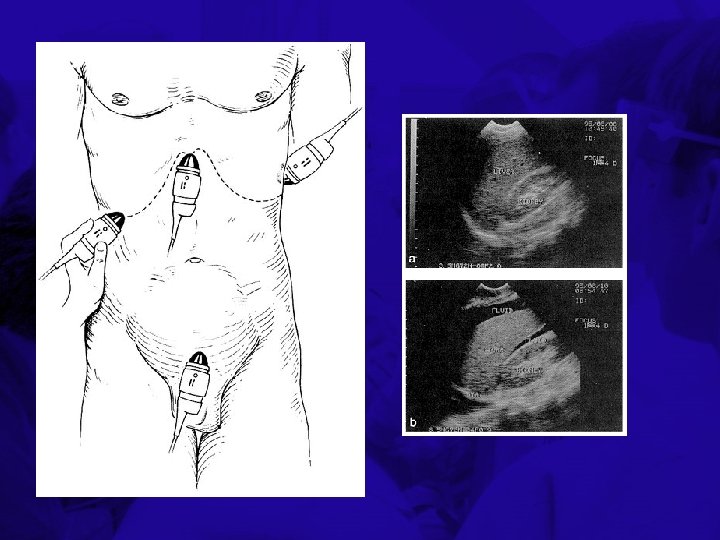

Adjuncts to the Primary Survey • Exams during or after primary survey to aid in identifying life-threatening injuries – Chest x-ray – Pelvis x-ray – Focused abdominal sonogram for trauma (FAST) – Diagnostic peritoneal lavage (DPL)